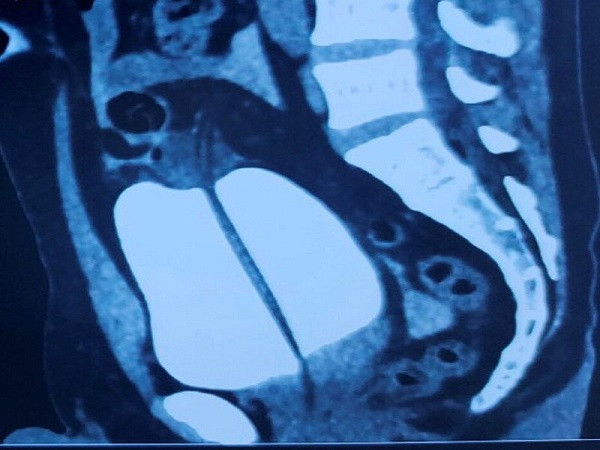

| Hình ảnh chụp CT của bệnh nhân N.V.T. Ảnh: Vietnamnet.vn. |

Tại đây, bệnh nhân T. được thăm khám lâm sàng và chỉ định làm các xét nghiệm, đánh giá cận lâm sàng. Bệnh nhân được chẩn đoán xác định vỡ bàng quang dẫn tới viêm phúc mạc và được chỉ định phẫu thuật.